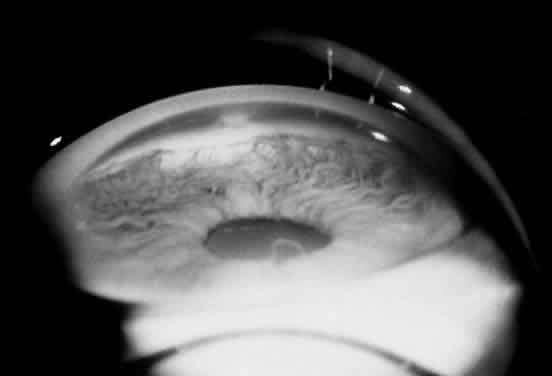

Ocular manifestations of the Axenfeld-Rieger syndrome include the presence of posterior embryotoxon and iris strands that attach to Schwalbe's line (Fig. 11). If the iris is normal, the condition is termed Axenfeld's anomaly. If iris defects are present, then it is classified as Rieger's anomaly. Iris findings in Rieger's anomaly may range from mild hypoplasia to full-thickness hole formation (Fig. 12). Glaucoma develops in approximately 50% to 60% of patients with Axenfeld-Rieger syndrome. When Rieger's anomaly is associated with systemic anomalies, it is known as Rieger's syndrome. Developmental abnormalities seen in Rieger's syndrome commonly affect the teeth and facial bones. These defects may include microdontia, hypodontia, and maxillary hypoplasia. Originally described as separate clinical entities, Axenfeld's and Rieger's anomaly are now considered to be variations in the spectrum of the same developmental disorder.

Fig. 11. Gonioscopic view of the iris processes in Axenfeld-Rieger syndrome. (Courtesy of James J. Reidy, MD)

Fig. 12. Rieger's syndrome. (Courtesy of James J. Reidy, MD)

A late arrest in the development of anterior chamber structures derived from neural crest cells is responsible for the ocular defects seen in Axenfeld-Rieger syndrome. Contracture of an abnormally retained primitive endothelial layer on the surface of the iris and anterior chamber angle, deposition of basement membrane by these endothelial cells, and incomplete development of the trabecular meshwork and Schlemm's canal are thought to be responsible for the iris changes, prominent Schwalbe's line, and glaucoma that are seen in this disorder. The systemic malformations seen in Rieger's syndrome are also secondary to a defect in neural crest cell development.